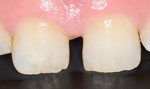

症例1(すきっ歯)

20代の患者さんでずっと前歯の隙間が気になっていてコンプレックスでしたと

術後非常に喜んでおりました。

回数3回 費用6,0000円

術前

術後